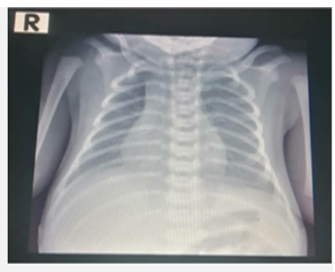

Metastatic Pulmonary Calcification with the Coexistence of known Esophageal Carcinoma: Case Report and Literature Review

Khurram Khaliq Bhinder, Sana Sayeed, Aroosa Kanwal, Nasir Khan

Abstract 32 | PDF Downloads 33 EPUB Downloads 28

Page 1224 - 1230